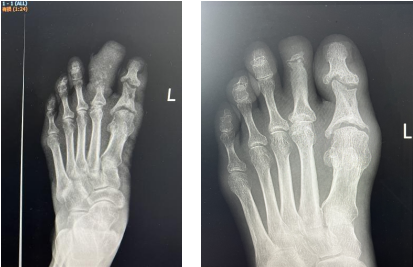

治疗前后对比

3个多月后,赵阿姨回到医院来拆掉外架,经伤趾DR治疗前后对比显示,其左足第二趾血供明显改善,创面完全愈合,伤趾还长出了新指甲,与之前肿胀、糜烂的足趾判若两“趾”。

治疗前后DR对比